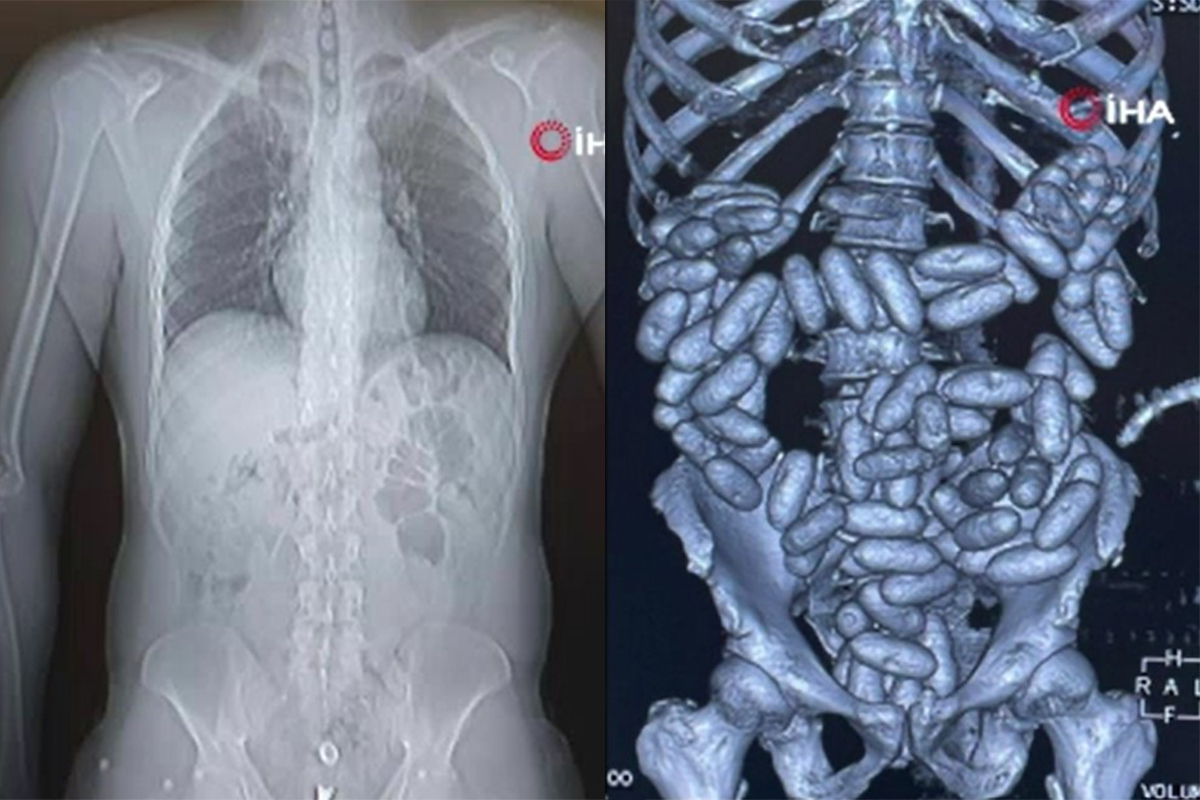

Cihazda, şüpheli yoğunluk tespit edilmesi üzerine zanlılar, muayene edilmek üzere hastaneye götürüldü. Burada yapılan tetkikler ve röntgen kontrollerinde, yolcuların sindirim sisteminden daralı ağırlığı 3 kiloyu bulan 360 kapsül içinde eroin tespit edildi.